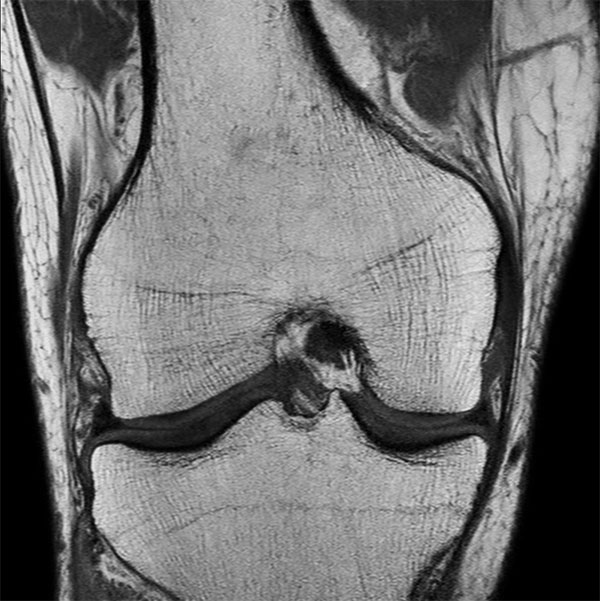

Knee Imaging with Cartilage Assessment

Middle aged board surfer presents with chronic knee pain. X-Ray shows no abnormalities. Follow-up MR examination requested.